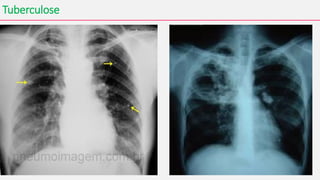

Tuberculose

• A tuberculose é uma das doenças infecciosas documentadas de mais

longa data e que continua a afligir a Humanidade nos dias atuais.

• Causada pelo Mycobacterium tuberculosis

• A tuberculose pulmonar é a forma mais frequente e generalizada da

doença. Porém, o bacilo da tuberculose pode afetar também outras

áreas do nosso organismo, como, por exemplo, laringe, ossos e

articulações, pele (lúpus vulgar), gânglios linfáticos, intestino e sistema

nervoso.

• A tuberculose miliar consiste num alastramento da infecção a diversas

partes do organismo, por via sanguínea.

• A infecção pelo M. tuberculosis se inicia quando o bacilo atinge

os alvéolos pulmonares.

• A resposta imunológica do organismo mata a maioria dos bacilos, levando à

formação de um granuloma. Os nódulos de tuberculose são pequenas lesões

que consistem em tecidos mortos de cor acinzentada contendo a bactéria da

tuberculose.

• Normalmente o sistema imunológico é capaz de conter a multiplicação do

bacilo, evitando sua disseminação em 90% dos casos.

• Cerca de 5% das pessoas infectadas vão desenvolver a doença nos dois

primeiros anos, e outras 5% vão desenvolvê-la ainda mais tarde.

• Entre os sintomas, estão tosse com secreção, febre (mais comumente

ao entardecer), suores noturnos, falta de apetite, emagrecimento,

cansaço fácil e dores musculares. Dificuldade na respiração,

eliminação de sangue e acúmulo de secreção na pleura pulmonar.

• A transmissão pode ser interrompida isolando-se pacientes com a